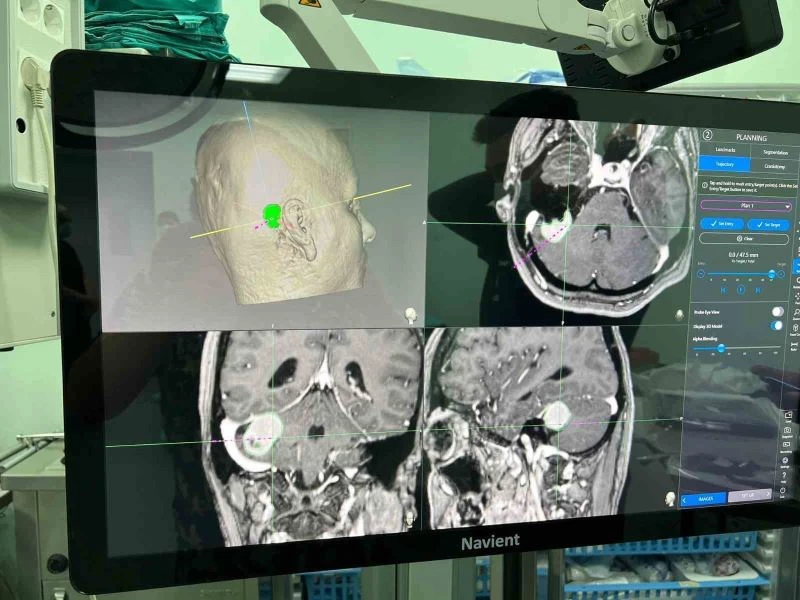

Daha önce teknik yetersizlikler nedeniyle Niğde’de yapılamayan ve hastaların başka şehirlere sevk edildiği köşe beyin tümörü ameliyatları, eksik cihazların giderilmesi ile artık Niğde’de yapılabiliyor. Baş ağrısı ve baş dönmesi şikayetleri ile hastaneye başvuran 43 yaşındaki Figen Turgut’a yapılan tetkikler sonucu köşe tümörü olarak tabir edilen kulak arkasında beyin zarından kaynaklı bir kitle tespit edildi. Yapılan tetkiklerin ardından ameliyat kararı alan Beyin Cerrahi Uzm. Op. Dr. Burak Yürük, Türkiye’de ileri merkezlerde kullanılan cihazların hastaneye alınması ile hastanın ameliyatını gerçekleştirdi. Kısa sürede sağlığına kavuşan ve yarın taburcu olması beklenen hastayı Başhekim Dr. Öğretim Üyesi Yakup Çetinkaya ziyaret etti.

Operasyonu gerçekleştiren Beyin ve Sinir Cerrahi Uzmanı Op. Dr. Burak Yürük de, "Burada bir takım eksik teknik imkanları sağlamak adına bunun planlamasını yaptık. Türkiye’de birçok ileri merkezde olan dediğimiz cihazları kullanarak ameliyatın daha güvenli olmasını sağladık. Daha sonrasında hastanın bir takım ameliyat öncesi tetkiklerini yaptık. Bunlar Türkiye’de ileri merkezlerde olan tetkikler. Hastanın ameliyattan sonra bu tür ameliyatlarda korktuğumuz birtakım sinir yaralanmaları olur ve biz böyle bir yaralanmayla karşılaşmadık konforu arttırıcı cihazların yardımıyla" dedi.

Beyin zarından kaynaklı tümörü olan hastanın 1 gün yoğun bakımda kaldığını, yarın da taburcu edileceğini söyleyen Op. Dr. Burak Yürük, "Bu ameliyatın daha konforlu, güvenli olması için yüze, yanağa ve dile giden sinirleri montize ettik. Görüntülemesini yaptık. Aynı zamanda ince kesik tetkiklerini elde ederek hem ameliyat sırasında, hem ameliyat sonrasında bize yol gösterici navigasyon dediğimiz bir haritalama yaparak tümörün tamamına yakınını boşalttık. Ameliyat sonrası filminde de hasta, mevcut baskı oluşturacak bir kitle lezyonu artık göstermiyor" diye konuştu.